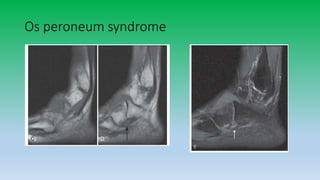

Os peroneum:

• The os peroneum is a common sesamoid bone located in the

peroneus longus tendon as it passes under the

cuboid. Painful os peroneum syndrome presents with marrow edema

of the ossicle with surrounding soft tissue edema, best shown with

a luid-sensitive MRI sequence targeted to the lesion

Os peroneum syndrome

• 33. Os peroneum: • The os peroneum is a common sesamoid bone located in the peroneus longus tendon as it passes under the cuboid. Painful os peroneum syndrome presents with marrow edema of the ossicle with surrounding soft tissue edema, best shown with a luid-sensitive MRI sequence targeted to the lesion